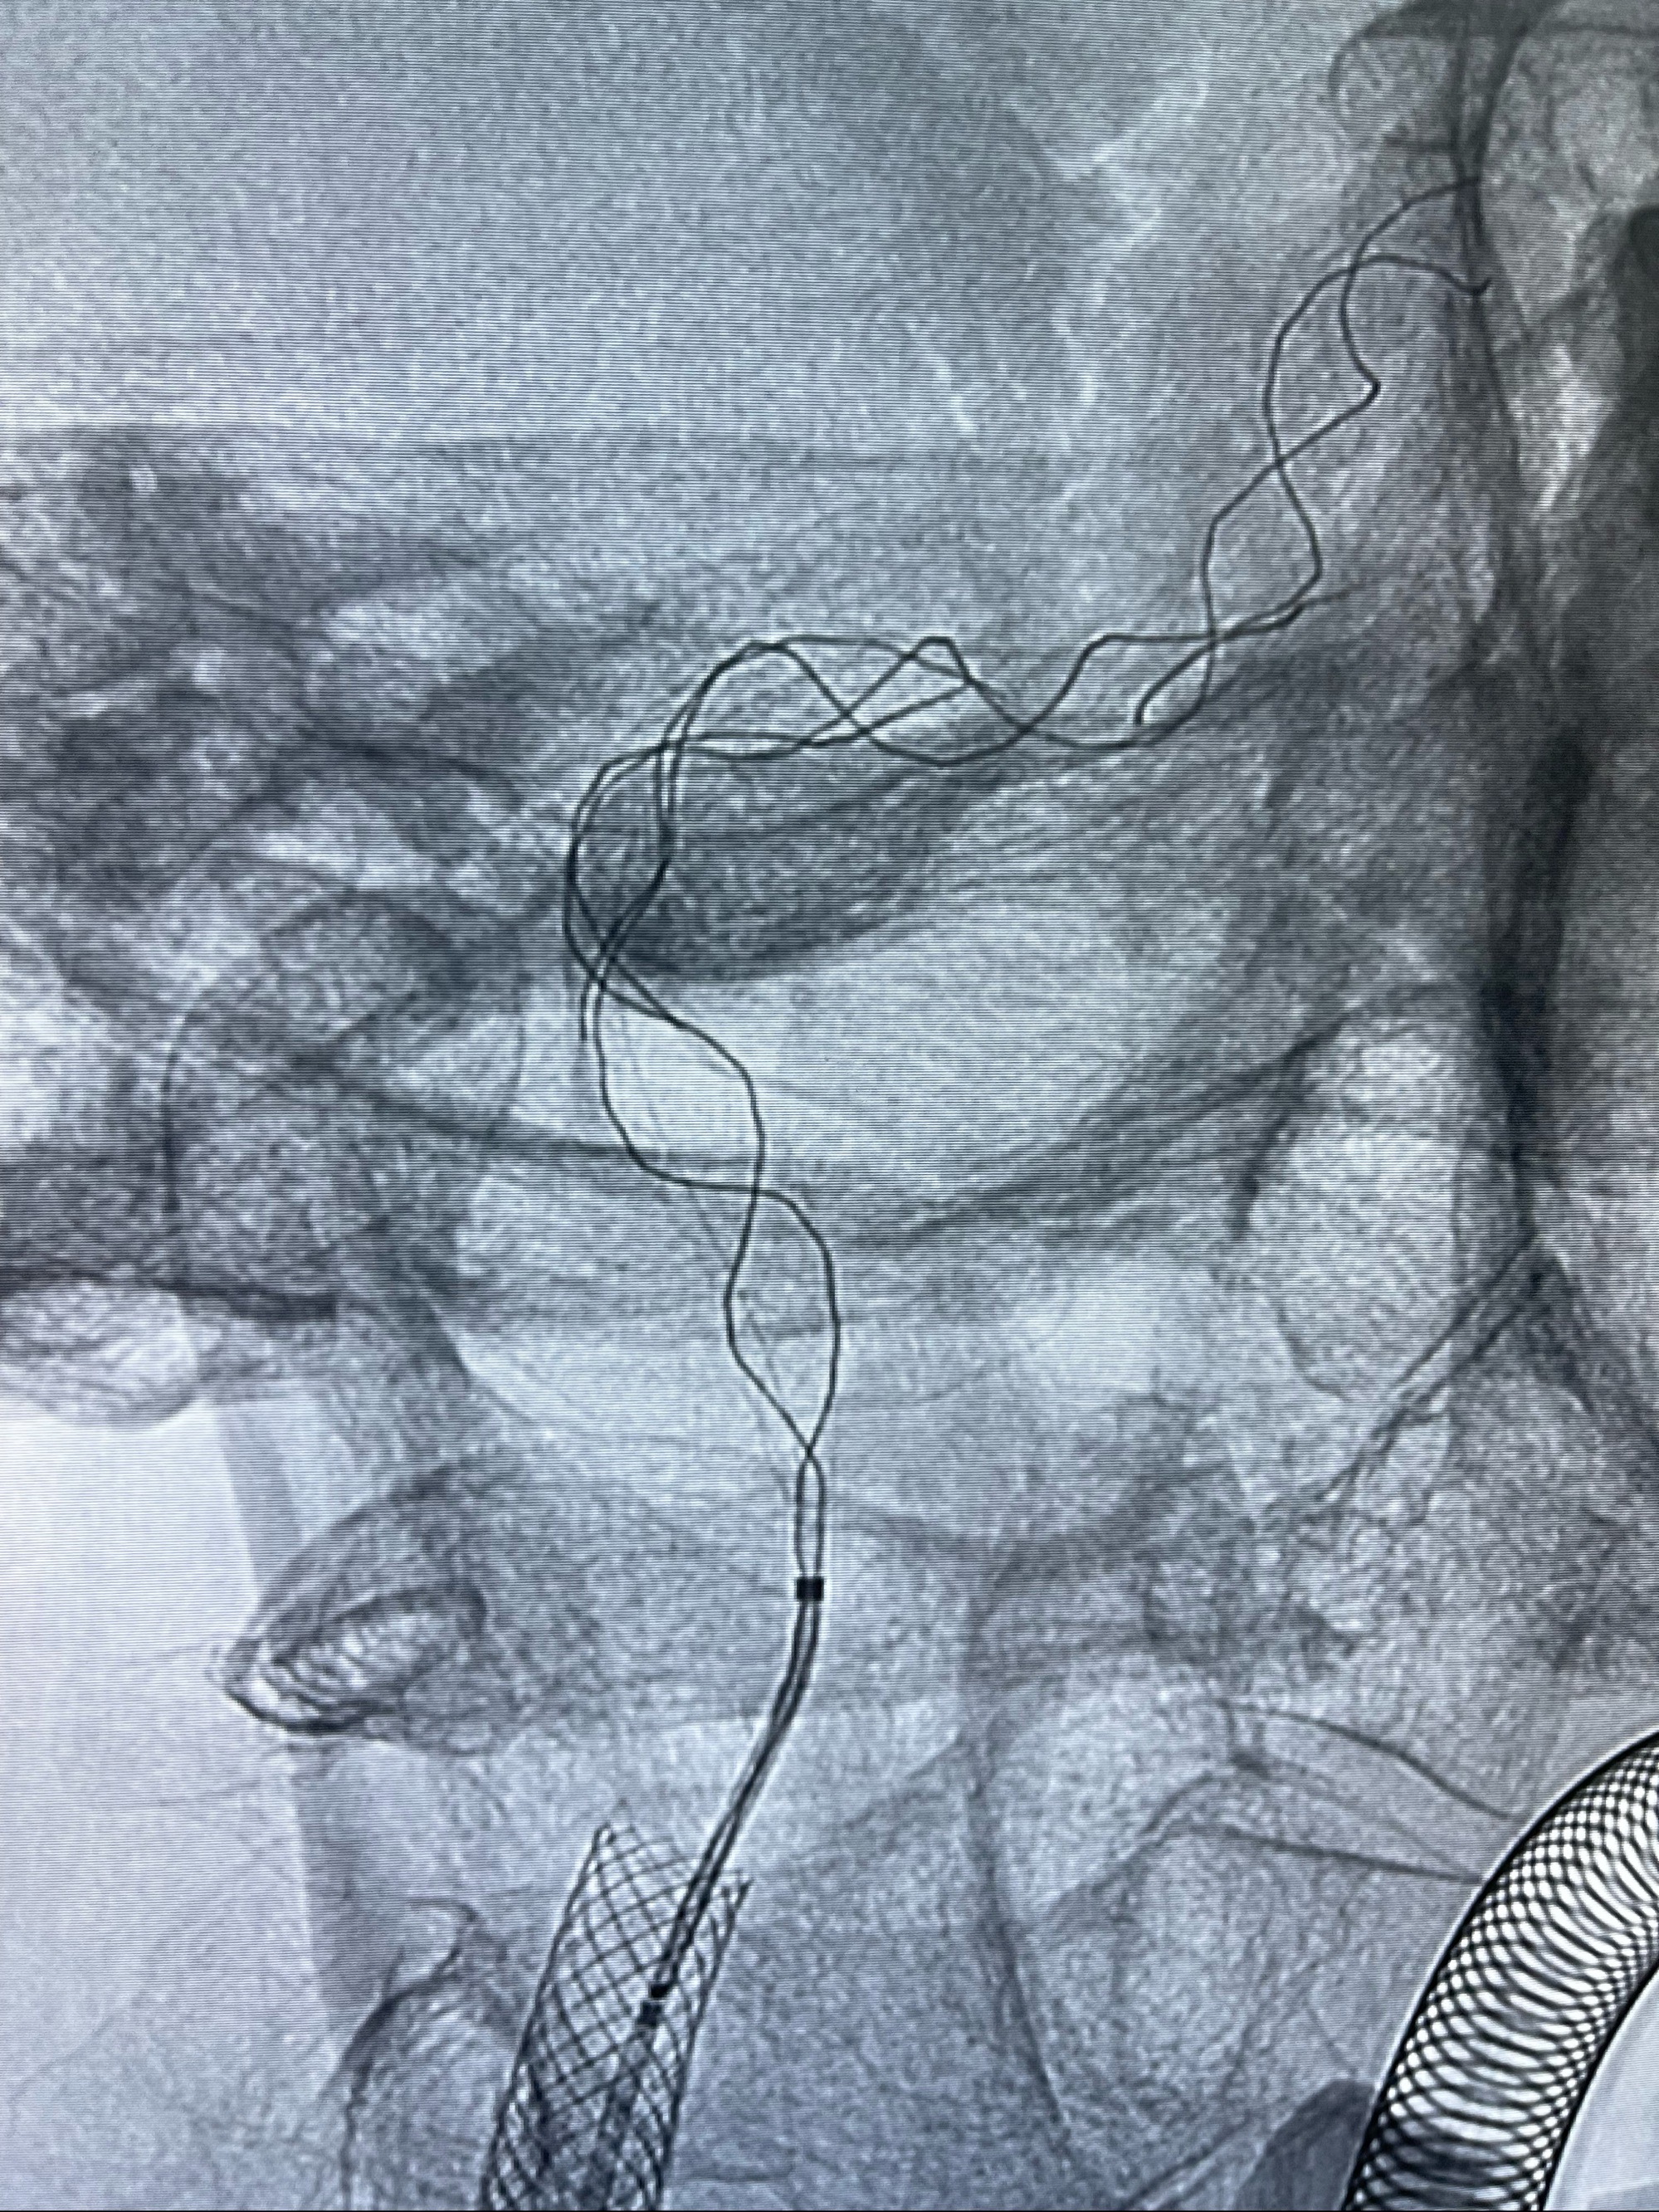

088NeuroMAX100cm长鞘在125cmMPA及黑泥鳅导丝引导下超选择性插入右侧颈内动脉支架内

经导引导管造影显示支架远端颈内动脉不规则狭窄伴局部充盈缺损,同时行全身肝素化5ml

路径图下4-20mm球囊在导丝引导下超选择性至狭窄段,以6-8个大气压扩张,持续30s

泄除球囊造影显示局部管腔扩张佳